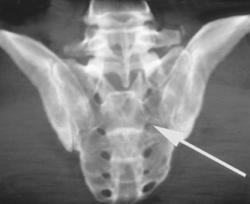

Symphysis Fractures With Diastasis and Pelvic Ring Injury